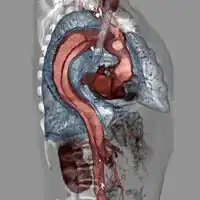

Computed tomography

Computed tomography angiography is a fast, noninvasive test that gives an accurate three-dimensional view of the aorta. These images are produced by taking rapid, thin-cut slices of the chest and abdomen, and combining them in the computer to create cross-sectional slices. To delineate the aorta to the accuracy necessary to make the proper diagnosis, an iodinated contrast material is injected into a peripheral vein. Contrast is injected and the scan performed using a bolus tracking method. This type of scan is timed to an injection to capture the contrast as it enters the aorta. The scan then follows the contrast as it flows through the vessel. It has a sensitivity of 96 to 100% and a specificity of 96 to 100%. Disadvantages include the need for iodinated contrast material and the inability to diagnose the site of the intimal tear.

Chest CT with descending (type B Stanford) aortic dissection (red circle)